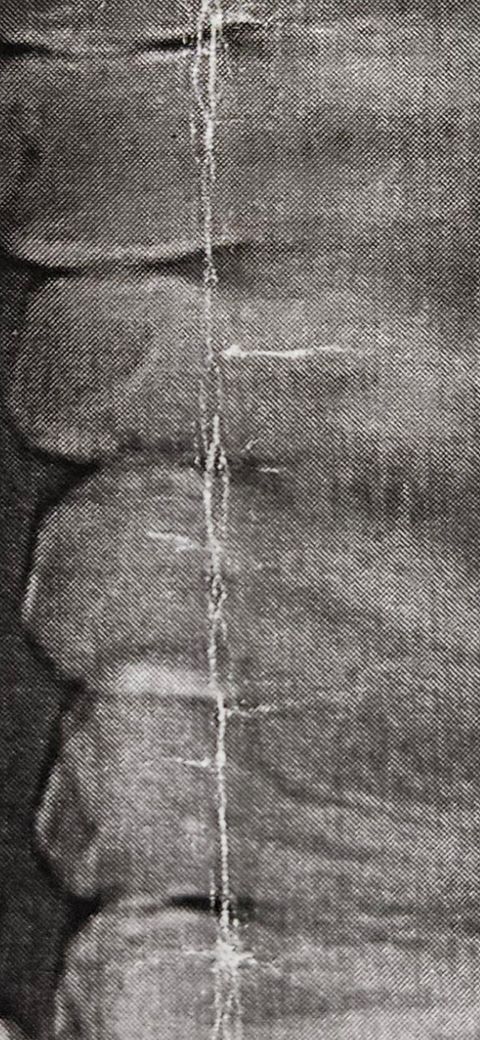

11월 4일에 찍은 파노라마 일부입니다. 인접면충치인데 제가 11월말에 치료예정인데 그 전에 신경에 닿거나 근접해서 신경치료를 하게될 가능성이 얼마나 되나요?

• 1번 째 사진

사진이 너무 흐리기는 하지만 2주 정도만에 충치가 급격하게 진행될 가능성은 낮은 편입니다.

사진이 너무 흐려서 제대로 치아 상태를 파악하기가 어려워 보입니다 .인접면 충치가 잇다면 최대한 빨리 치료를 하시는게 좋을것같습니다.

그렇게 큰 인접면 충치로 보이지는 않습니다만 파노라마 말고 작은 치근단 사진 찍어봐야 정확히 알 수 있습니다